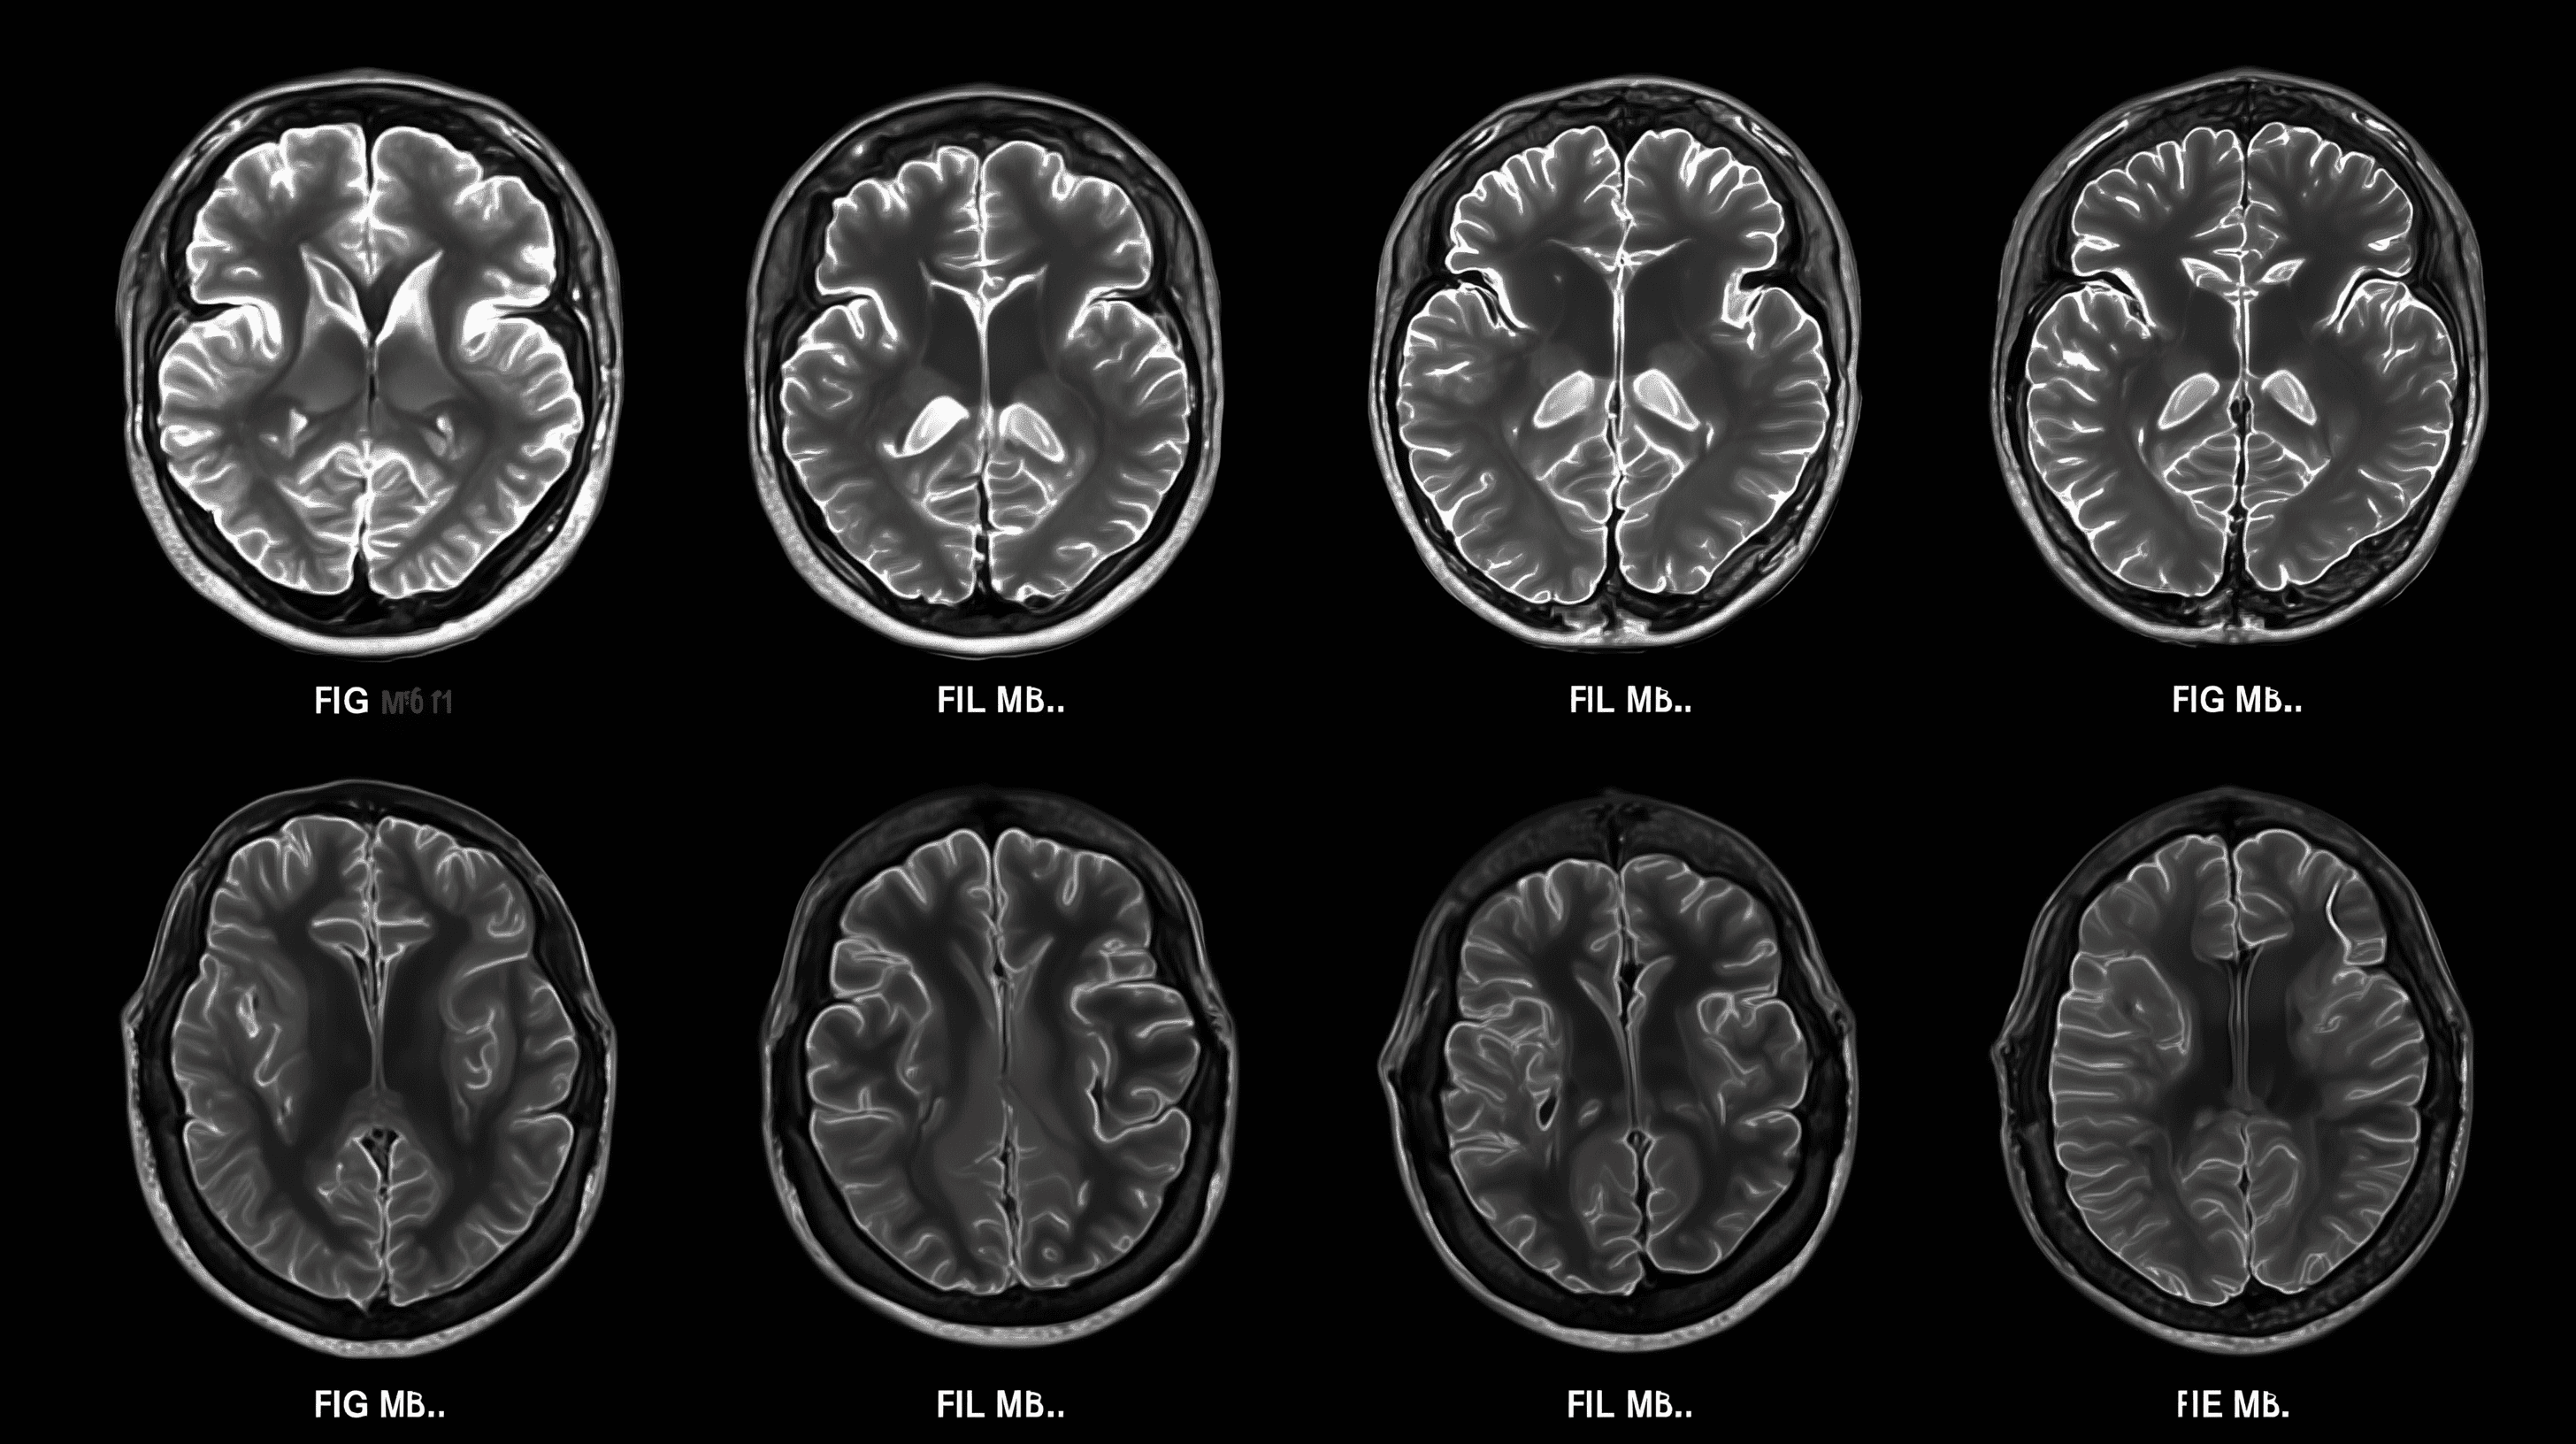

- In 2016, Chairman Vincent Chiang initiated a collaboration with Prof. Ying-Jui Ho from Chung Shan Medical University to develop a novel therapeutic candidate for Parkinson’s disease (PD), Parkinson’s disease dementia (PDD), and dementia with Lewy bodies (DLB). The project aims to address the underlying causes of these neurodegenerative disorders and to develop an innovative treatment capable of modifying disease progression.

- In 2017, an Investigational New Drug (IND) application was submitted to the U.S. FDA, enabling the launch of a multicenter, double-blind Phase II clinical trial in patients with PDD. The study progressed to the unblinding stage in the second quarter of 2025.